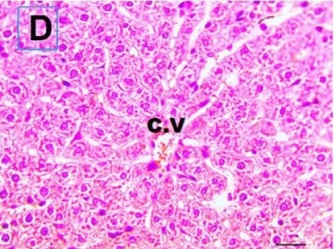

Put the liver tissue section under a microscope, and you can see that cisplatin can cause liver congestion (the blood that should return to the heart is blocked and stagnates in the hepatic veins), cell degeneration (vacuoles appear, which is the earliest change in cellular injury), apoptosis and necrosis, but these conditions can also be alleviated by using Ganoderma lucidum.

Figure 2 Effects of cisplatin and Ganoderma lucidum on hepatocytes